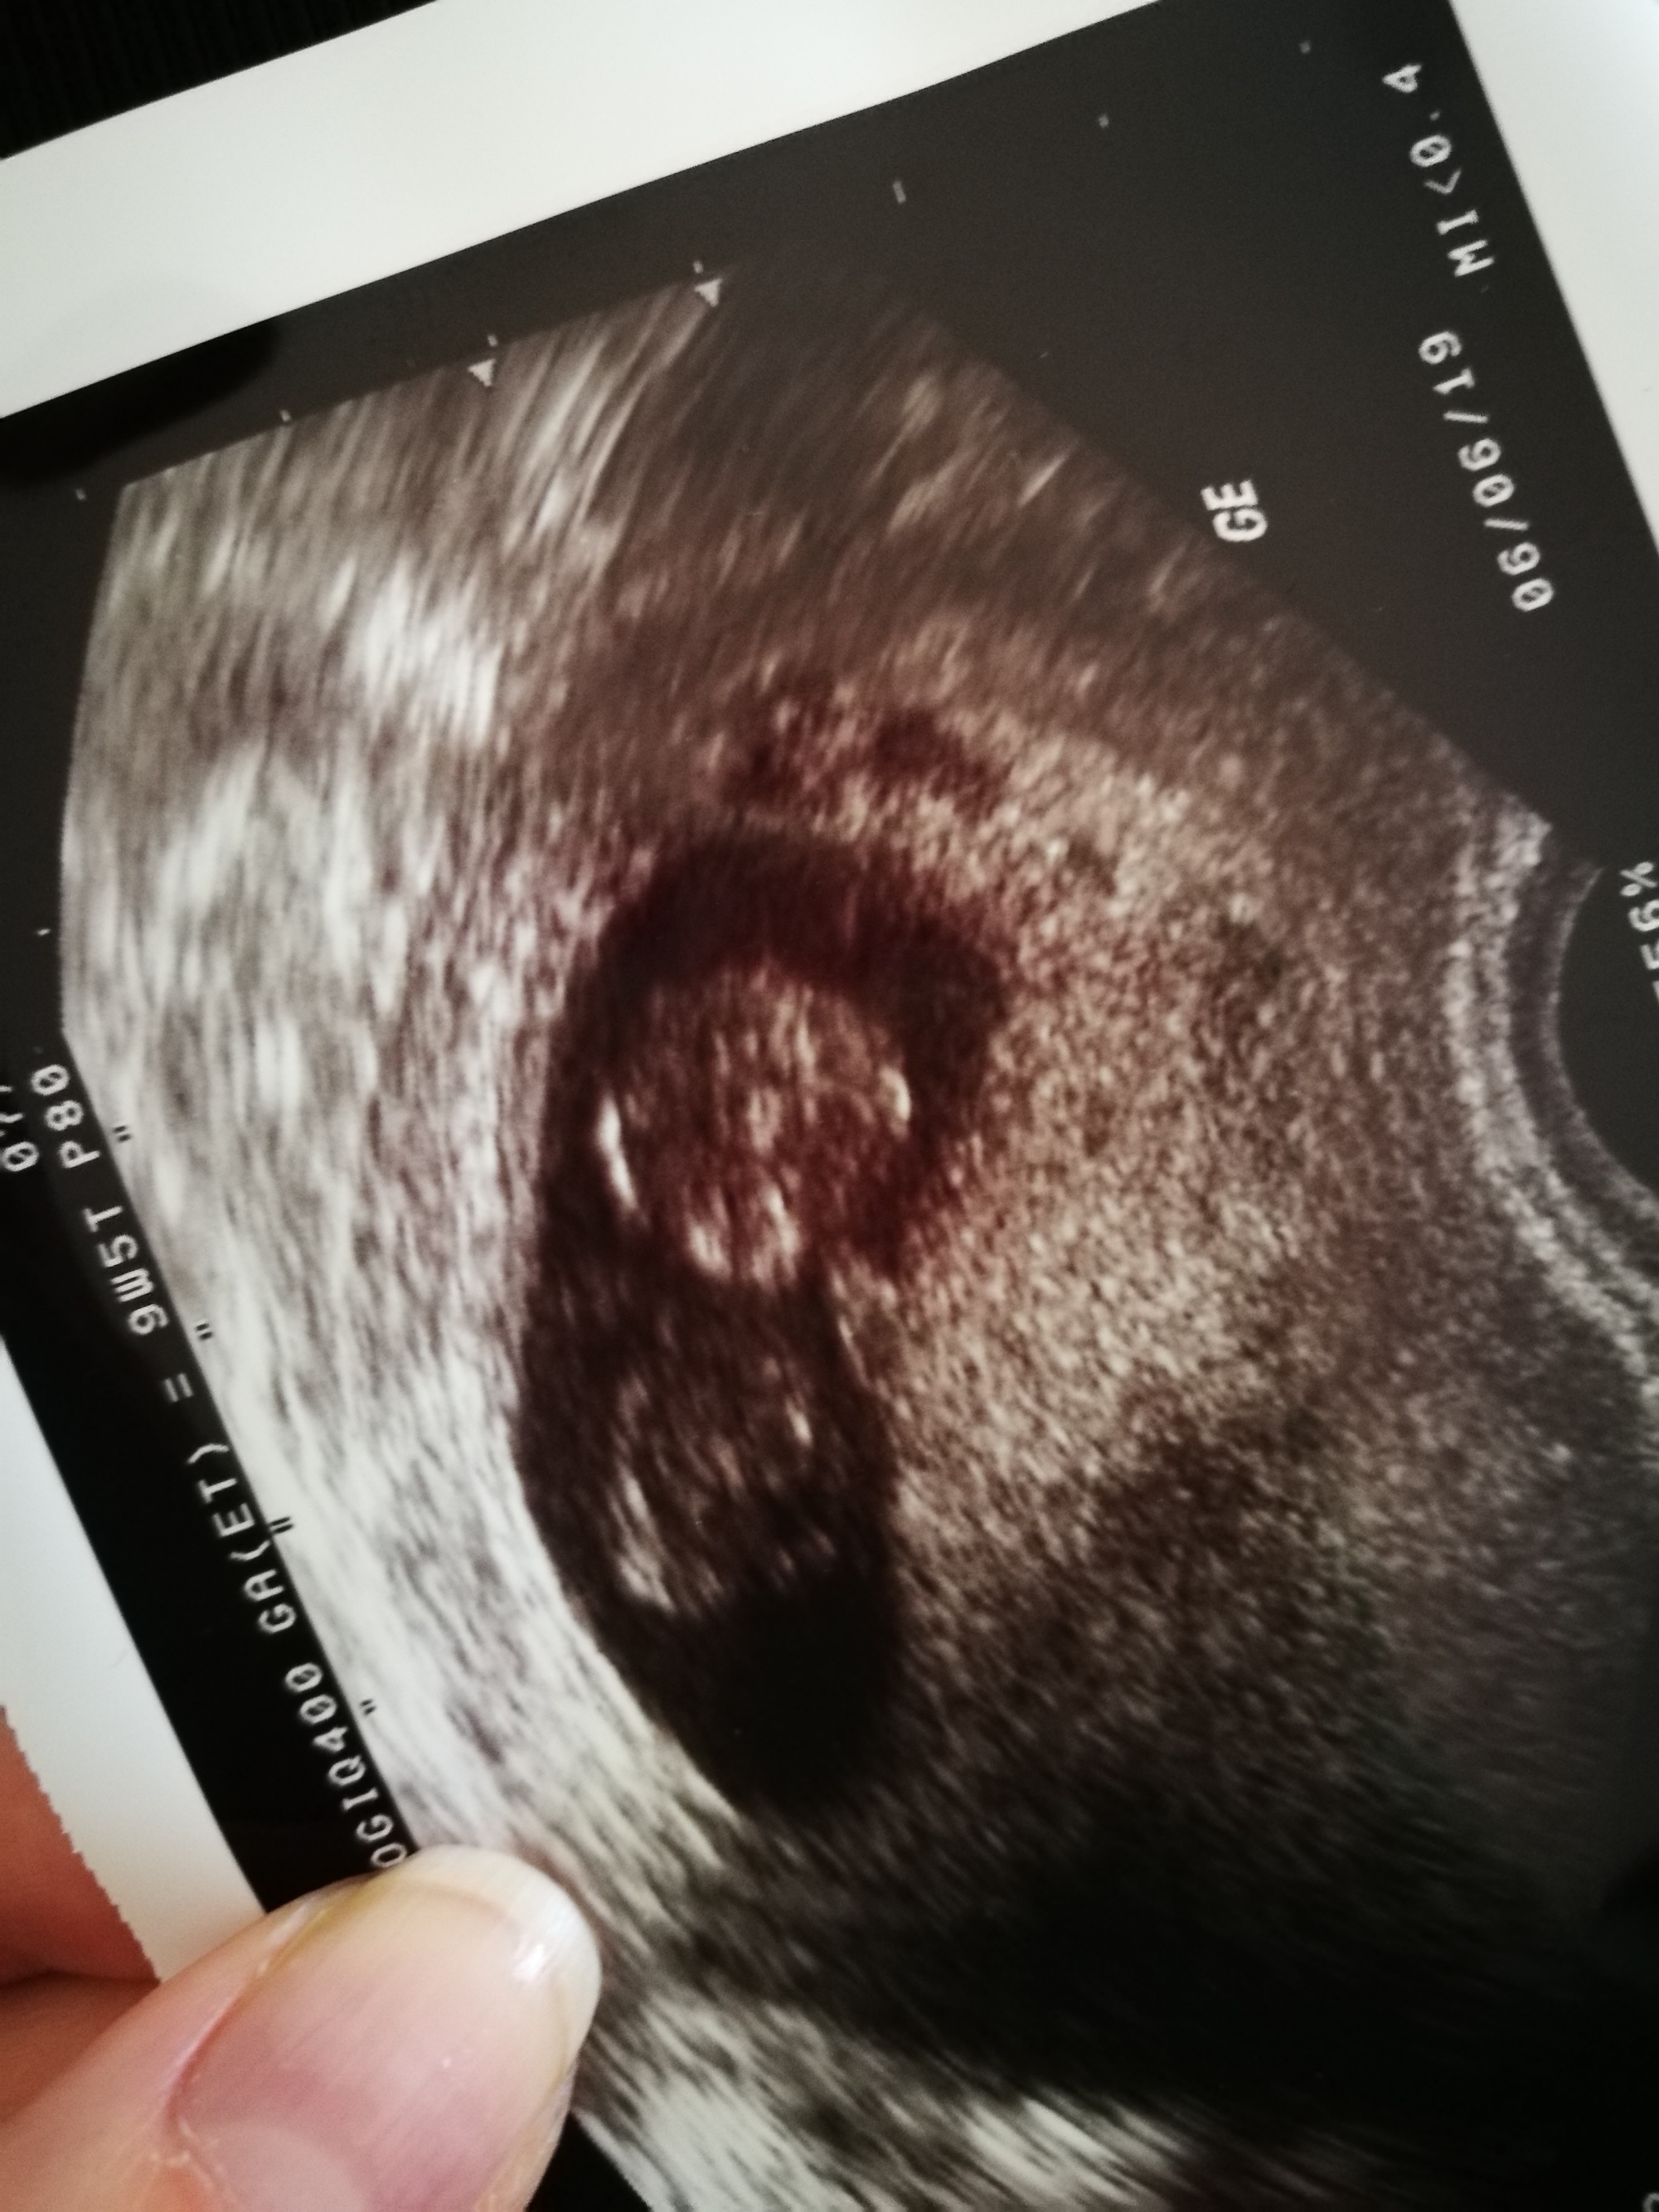

A tak sie jeszcze zastanawiam. Bo jak ogladam zdjecia z usg to pęcherzyk ciazowy jest okrągły. A moj dzisiaj byl taki plaski i dluuugi...ale gin nic nie powiedziala na ten temat...któraś z Was tez tak miala?

Na synka taki był :)

Kulka u gory to glowka, na dole brzuszek a kropki obok glowy to raczki :)